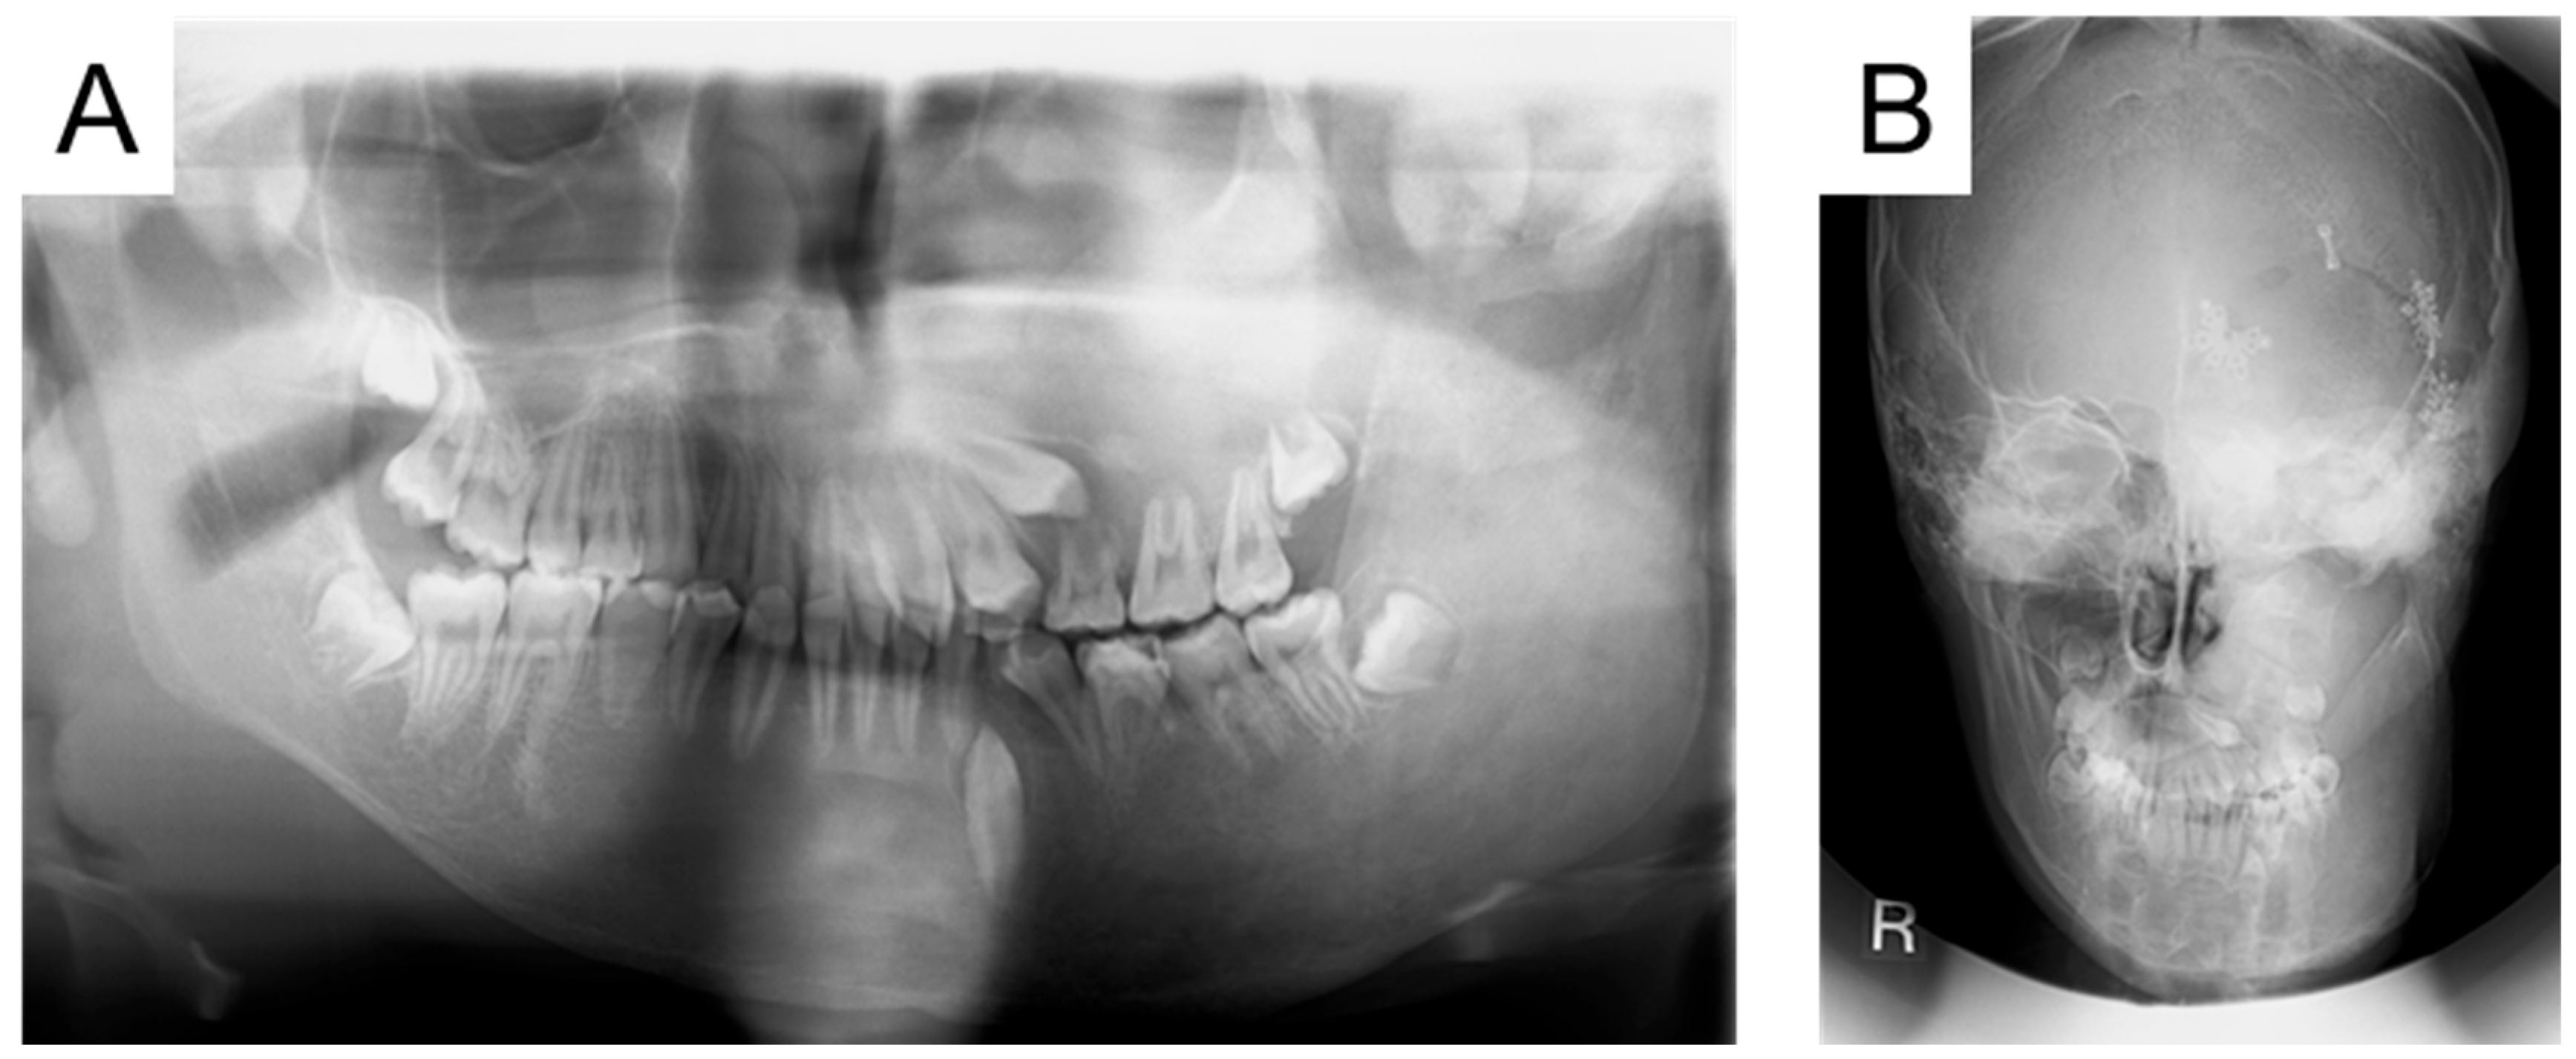

| 5 y | Swelling in the left cheek region |

| 9 y | Diagnosis of MAS and precocious puberty, and start of bisphosphonate therapy |

| 11 y | Optic canal decompression surgery |

| 13 y 7 m | First visit to our department |

| 15 y 6 m | Left maxillary primary first molar extraction |